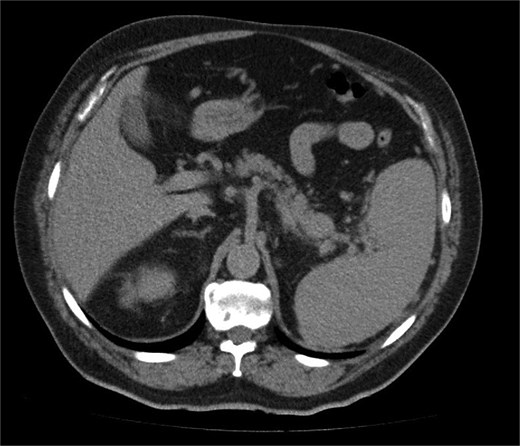

A 68-year-old man with a prior history of left radical nephrectomy for RCC was incidentally found to have a pancreatic abnormality on surveillance imaging. A contrast-enhanced computed tomography (CT) scan of the abdomen showed a soft tissue lesion in the pancreatic tail measuring 2.4 × 2.7 cm, radiologically suspicious for a primary pancreatic neoplasm (Fig. 1). The left renal bed appeared clear.

A contrast-enhanced CT scan of the abdomen (axial image) showing a soft tissue lesion in the pancreatic tail measuring 2.4 × 2.7 cm, radiologically suspicious for a primary pancreatic neoplasm.